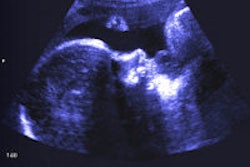

This month, June 2018, marks the 60th anniversary of U.K. researcher Dr. Ian Donald's classic article on ultrasound, published in the Lancet. Today, we cannot imagine a hospital without access to ultrasound. Ultrasound has changed medical management and diagnosis for the better, enabling more accurate noninvasive diagnosis without radiation in many medical scenarios, and not just for the obstetric patient.

Few people can really claim to have revolutionized medical practice, but Donald is one of them. His legacy is all around us in every country, and has helped make childbirth safer worldwide by enabling accurate antenatal diagnosis so that appropriate care can be tailored for the pregnant mother and the newborn child.

Along with Tom Brown, the engineer form Kelvin and Hughes, he started his experiments with ultrasound, resulting in building the first machine with Brown in 1958. This led to the ultrasound images first published in the 1958 Lancet article written with Dr. John McIver (registrar in the unit) and Brown.